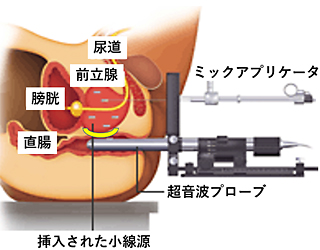

密封小線源療法とは何ですか?

小さな線源を前立腺内に挿入し、前立腺内のがん病巣へ線源から放射線を照射する放射線治療です。

放射線治療の場合、がんのある前立腺のみに照射したいのですが、前立腺は上に膀胱、後ろに直腸が接しているため、従来の外部照射療法では前立腺だけでなく周辺の臓器にも多くの線量の放射線がかかってしまい、また密封小線源治療(シード治療)でもある程度の線量がかかってしまい、かかったところに有害事象(副作用)が出現していました。

- 前立腺と直腸の間の隙間に注射針を挿入する操作を観察できるように、超音波プローブを挿入します(図:注入前)。

- 肛門開口部より2cm上部の皮膚から注射針を挿入。超音波を見ながら、直腸尿道筋を貫通し、前部直腸壁と前立腺の間の直腸周囲脂肪組織に達するように注射針を操作します。

- 注射針の位置を超音波画像で観察し、針先が直腸周囲脂肪組織の中にあることを確認し、生理食塩水を少量注入して空間を作成。その後にSpaceOAR®ハイドロゲルを前立腺と直腸壁の間(Denonvilliers筋膜 (腹膜前立腺筋膜))と直腸前壁の間)にスムーズに連続注入します(図:注入後)。